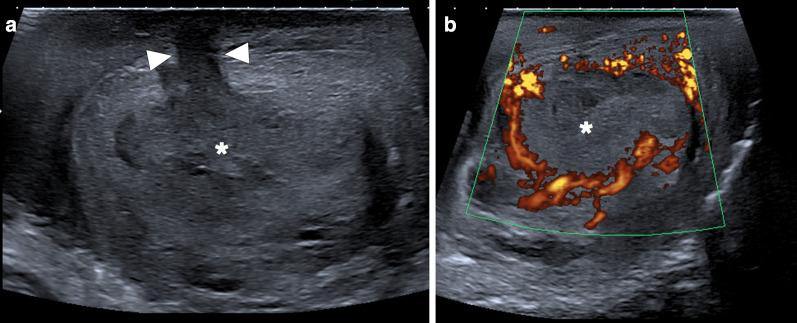

Identifying the deceiver: the non-neoplastic mimickers of genital system neoplasms.

Tumors of the genital system are common and imaging is of crucial importance for their detection and diagnosis. Several non-neoplastic diseases may mimic these tumors and differential diagnosis may be difficult in certain cases. Misdiagnosing non-neoplastic diseases as tumor may prompt unnecessary medical treatment or surgical interventions. In this article, we aimed to present the imaging characteristics of non-neoplastic diseases of the male and female genital systems that may mimic neoplastic processes. Increasing awareness of the imaging specialists to these entities may have a severe positive impact on the management of these patients.